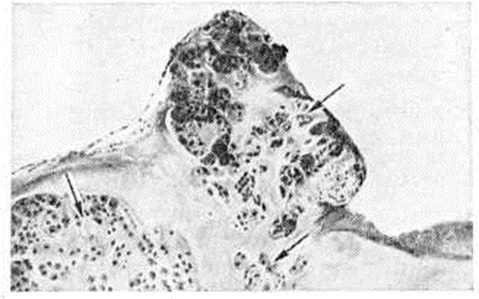

Макроскопически при Хондроматоз суставов ограниченные или обширные участки синовиальной оболочки покрыты узелками и диффузными возвышениями плотной консистенции. Отдельные узелки выступают над поверхностью синовиальной оболочки в виде полипов на ножке. Некоторые из них отшнуровываются и располагаются в полости сустава в виде свободных внутрисуставных телец величиной от нескольких миллиметров до 1—2 сантиметров в диаметре. Внутрисуставные тельца имеют округлую и овальную форму, гладкую поверхность белого или желтоватого цвета. Количество таких телец в суставе может достигать десятков и сотен. При опухолевидной форме Хондроматоз суставов внутрисуставные тела имеют вид крупных (до 3—5 сантиметров в диаметре) бугристых образований, состоящих из сливающихся узлов и долек хрящевой ткани. Микроскопически синовиальная оболочка утолщена, с гиперплазированными ворсинками. В ней отмечается инфильтрация лимфоидными и плазматическими клетками, обусловленная реактивным синовитом (смотри полный свод знаний). Отдельные ворсинки или вся толща синовиальной оболочки содержат очаги хрящевой ткани (смотри полный свод знаний) в виде мелких узелков и островков (рисунок 1). Хондроматозные очаги состоят из межуточного вещества с беспорядочно расположенными в нем хрящевыми клетками. Иногда архитектоника хондроматозных очагов отдалённо напоминает суставной хрящ, реже — хондрому (смотри полный свод знаний). В крупных очагах часто обнаруживают зоны обызвествления (смотри полный свод знаний: Кальциноз) и костеобразования (смотри полный свод знаний: Оссификаты). Могут встречаться очаги, состоящие только из костной ткани, представленной отдельными костными перекладинами или сетью перекладин пластинчатого строения с жёлтым, реже красным, костным мозгом в межбалочных пространствах. Свободные внутрисуставные тельца состоят из гиалинового хряща, реже — из гиалиновой и волокнистой хрящевой ткани. Поверхность внутрисуставных телец покрыта слоем волокнистой соединительной ткани, образующей капсулу. Иногда эта ткань напоминает перихондр и, видимо, служит источником образования хрящевого вещества. Обызвествление наблюдается в форме очагов или полос, что указывает на периодичность отложения солей кальция.